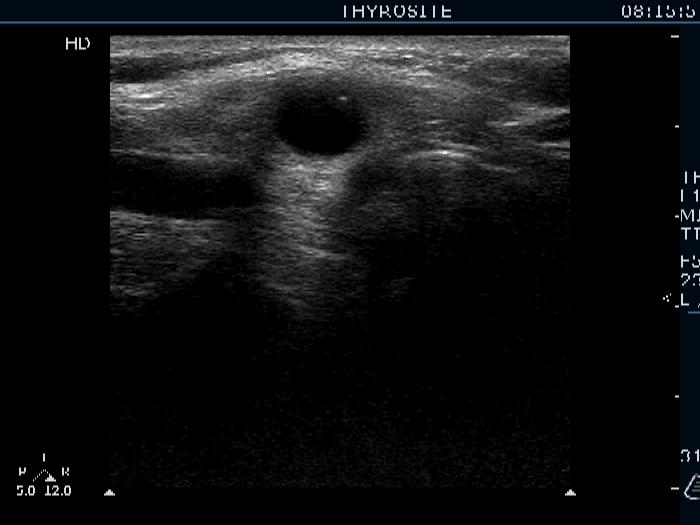

Lower part of the right lobe, trasnverse view. This is a cystic lesion.